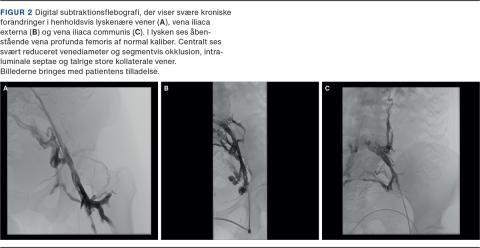

Endovaskulær behandling, dvs. ballondilatation og stentning, udføres for at genetablere det centrale venøse afløb fra ekstremiteten. Indsættelse af en stent forudgås af prædilatation af det obstruerede venesegment med højtryksballon og efterfølges af efterdilatation af selve stenten, ligeledes med højtryksballon (Figur 2 og Figur 3). Dilatationen er smertefuld, og indgrebet foretages derfor ofte i generel anæstesi.

Billede